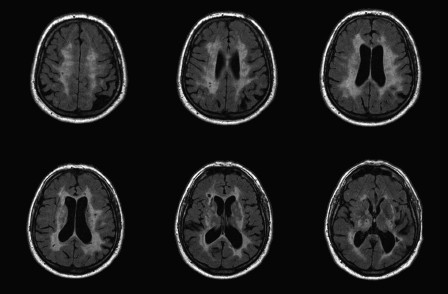

Um Hirnatrophie zu diagnostizieren, können verschiedene bildgebende Verfahren wie Magnetresonanztomographie (MRT) oder Computertomographie (CT) verwendet werden. Diese Techniken ermöglichen es Ärzten, das Gehirnvolumen zu messen und Veränderungen im Laufe der Zeit zu beobachten.

Zur weiteren Bewertung des Gehirns kann eine Bildgebung wie eine Magnetresonanztomographie (MRT) oder eine Computertomographie (CT) durchgeführt werden. Diese Verfahren ermöglichen es, Veränderungen im Gehirnvolumen sowie strukturelle Abweichungen festzustellen. Aufgrund ihrer nicht-invasiven Natur sind MRT und CT weit verbreitete Diagnoseverfahren für die Einfache Hirnatrophie.